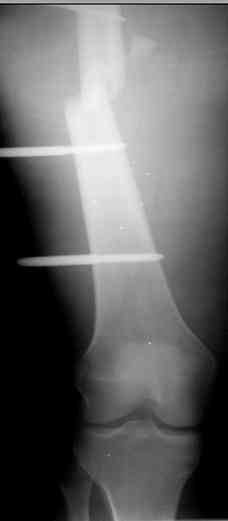

Коллеги! Прошу совета, какую тактику избрать при лечении.Больной 27 лет, мотоциклист. Поступил 23.04.10 ДЗ. О. перелом н.з левого бедра Gustillo 3b (c повреждение бедренной вены), О.Правого бедра Gustillo 2, з. фрагментарный перелом левой голени.При поступлении Hb 66 ISS 40, Фиксация стержневыми аппратами, сосудистые хирурги выполнили шов вены. Выполена резекция бедренной кости 9 см. На 7 сутки Желудочно-кмшечное кроветечение из стрессовых язв, 12 сутки флотирующий тромтоз 14 см установлен кава-фильтр. На 15 сутки закрытие ран местными тканями. Раны заживают первично. Воспаления на стержнях нет. В настоящий момент планируем. Переход со стержневых аппаратов на стержни с антибактериальным покрытием на правом бедре и левой голени. Левое бедро планируем продолжить фиксировать в стержневом аппарате.

Вопрос: что делать с левым бедром? Учитывая внутрисутавной характер перелома, дефект бедра 9 см.